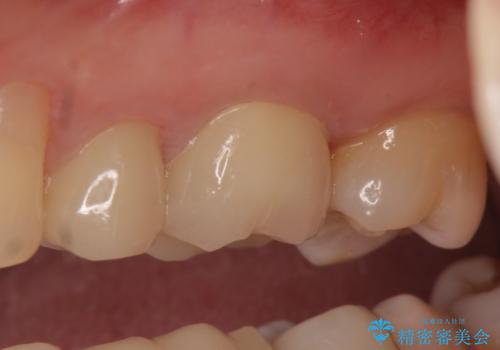

痛みの消失を確認後、オールセラミッククラウンによる補綴を行いました。

今回用いたオールセラミッククラウンはジルコニアフレームという白い素材の上にセラミックを盛っているため、審美性が非常に高いのが特徴です。

また、ジルコニアは人工ダイヤモンドの材料にも使われているほど高い強度を持っており、そのためオールセラミッククラウンは審美性だけでなく、奥歯やブリッジの補綴も可能とするクラウンです。